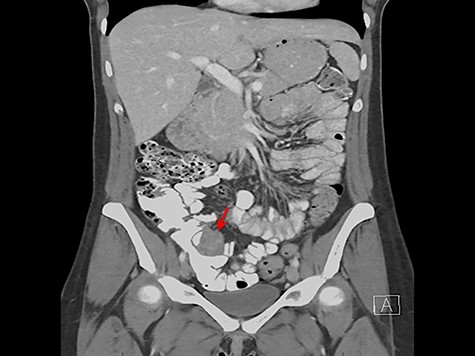

A 33-year-old female presented for surgical evaluation of a possible ileocecal mass and abnormalities found on endoscopy. She presented to an outside hospital 4 months prior to surgical consultation with symptoms of abdominal pain, diarrhea and hematochezia. Computed tomography (CT) imaging demonstratedthickening of the distal descending and proximal sigmoid colon and punctate pneumatosis concerning for ischemic colitis. Endoscopy with mucosal biopsy confirmed the diagnosis of colonic ischemia but also noted marked edema of the cecum and ileocecal valve. Her condition improved with non-surgical supportive care and her hematologic coagulation profile subsequently normalized after stopping oral contraceptive use. Repeat colonoscopy 2 months after hospital discharge confirmed resolution of ischemia but persistent abnormalities of the ileocecal area with cecal fullness and a prolapsed ileocecal valve (Fig. 1), with only lymphoid hyperplasia on biopsy. Repeat CT imaging was obtained and showed a

Colonoscopic image demonstrating cecal fullness with prolapsed ileocecal valve (arrow).

3.4 × 3.7 cm mass near the ileocecal valve (Fig. 2). Unable to rule out malignancy, surgical resection was recommended for tissue evaluation and the patient underwent laparoscopic right hemicolectomy.